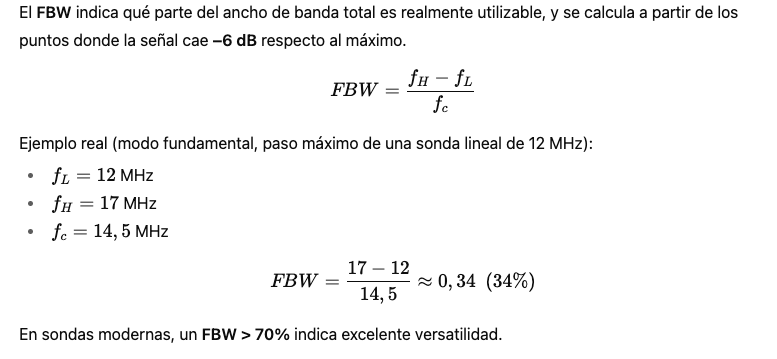

En este post vamos a abordar de forma completa una lesión muy frecuente en la práctica deportiva: el Tennis Leg.

Normal abajo, patológico arriba.